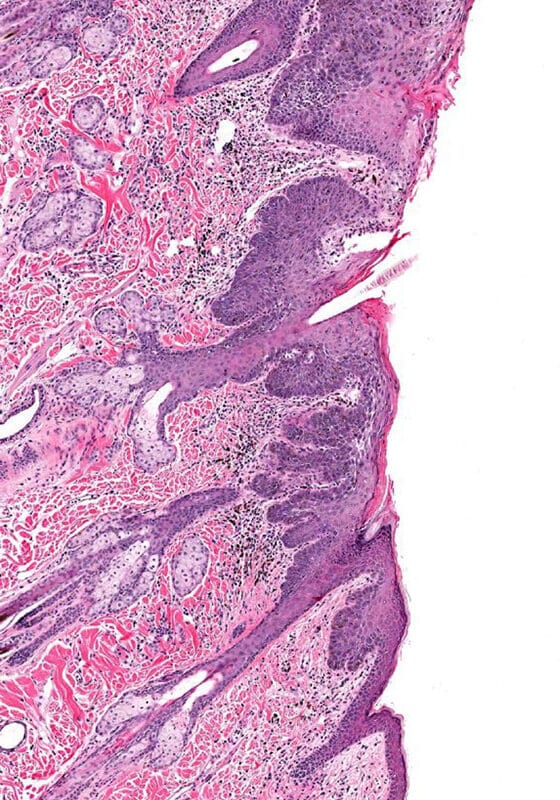

If we find a growth that is thick or looks like skin cancer during the exam, your dermatologist will likely perform a skin biopsy. Biopsy is very safe and is relatively painless.